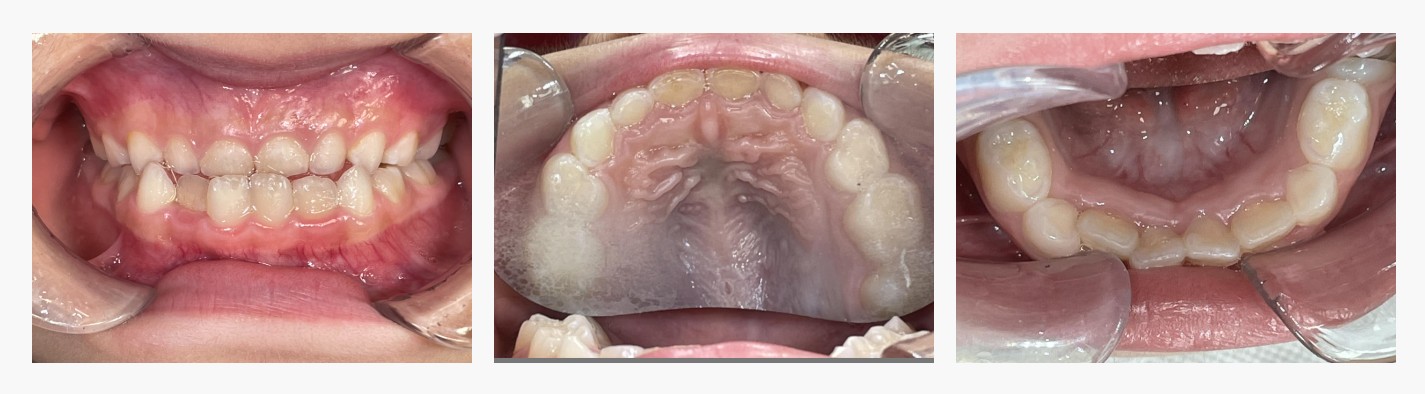

▼Before(治療前)

初診時は、上下の前歯が反対に咬み合う**反対咬合(受け口)**の状態で、あごの前方成長がやや強く、

将来的に骨格性の受け口へと進行するリスクがありました。